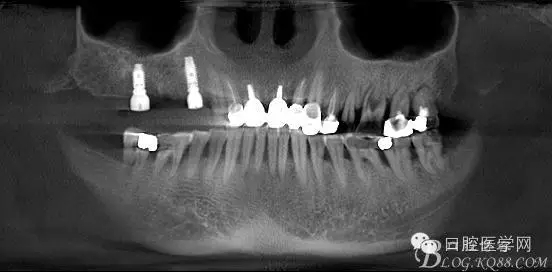

這是初診時候的CT片截圖。目標是14到16固定橋,別的牙齒先慢慢來,那么牙周肯定要做的,哪怕我要把14 16拔了,我也必須先去牙周科刮治。 在這里我感謝我們醫(yī)院的牙周科所有同事幫我們很多。刮治以后的牙齒拔掉即刻種植相對沒刮治過的牙齒肉芽會少很多,那么我在手術時候速度會快,會省力很多,我最討厭去刮很多肉芽,有時候搔刮肉芽的時間和精力比種牙的兩倍還多 而且很多肉芽會增加種植手術風險和術后反應最主要手術可以行云流水患者感覺良好 (我們一般會牙周治療和等待一段時間再約種植手術)者。

上圖14牙位和16牙位是我們想植入種植體的位置,考慮到47牙位還存在且沒有要拔掉的意思,那么我設計植體的時候適當往17牙位靠點。